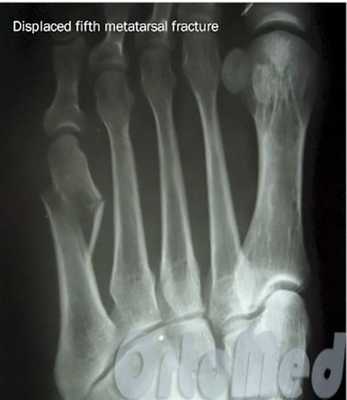

Плюсневые кости входят в группу мелких трубчатых костей скелета человека. Переломы плюсневых костей являются наиболее распространенным переломами костей стопы. А именно переломы основания пятой плюсневой кости, происходящие в результате инверсии стопы. Локализация перелома должна быть тщательно проанализирована врачом, так как лечение различных по локализации и характеру переломов достаточно сильно разнятся.

Так же переломы плюсневой кости стопы классифицируются по локализации, характеру перелома и наличию смещения:

- Переломы основания, тела или подголовчатые переломы плюсневых косте;

- Переломы плюсневой кости со смещением или без смещения;

- Переломы косые, поперечные, винтообразные, оскольчатые.

Если перелом сопровождается значительным смещением костных отломков (более чем на половину ширины плюсневой кости) решается вопрос об операции.

Операция при переломе плюсневой кости

Показанием к операции при переломе является смещение отломков плюсневой кости больше чем на половину ширины кости.